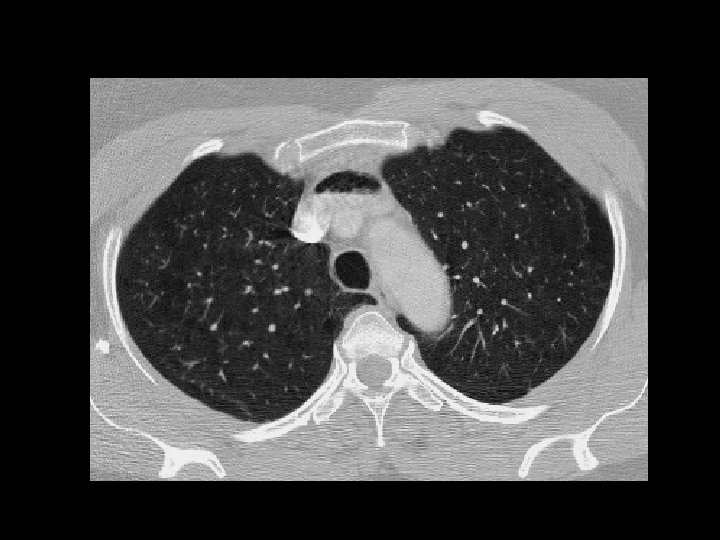

Sarcoidosis • Findings: – diffuse centrilobular nodules – nodular thickening of the interlobular septa – lymphadenopathy = “Garland’s triad” • ddx: – lymphangitic carcinoma